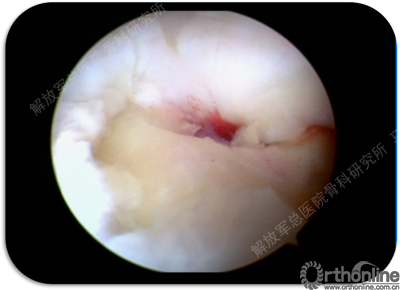

软骨已经完全破坏,损伤软骨下骨已经囊性变,囊内为滑模样组织。